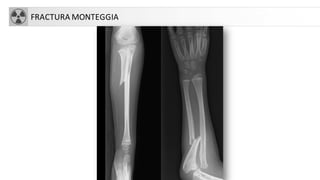

FRACTURASANTEBRAZO

• Se pueden presentar de forma conjunta (cúbito-radio)

• Fx Galeazzi: Fx diáfisis radial + Luxación radioulnar distal

• Monteggia: Fx cúbito (diafisaria)+Lux cabeza radio

• Complicaciones:

• Sd Volkmann

• Pseudoartrosis y consolidación defectuosa

• Artrosis

• Lesión N. mediano o cubital.

FRACTURA MONTEGGIA

FRACTURASANTEBRAZO • Se puedenpresentar de forma conjunta (cúbito-radio) • Fx Galeazzi: Fx diáfisis radial + Luxación radioulnar distal • Monteggia: Fx cúbito (diafisaria)+Lux cabeza radio • Complicaciones: • Sd Volkmann • Pseudoartrosis y consolidación defectuosa • Artrosis • Lesión N. mediano o cubital.